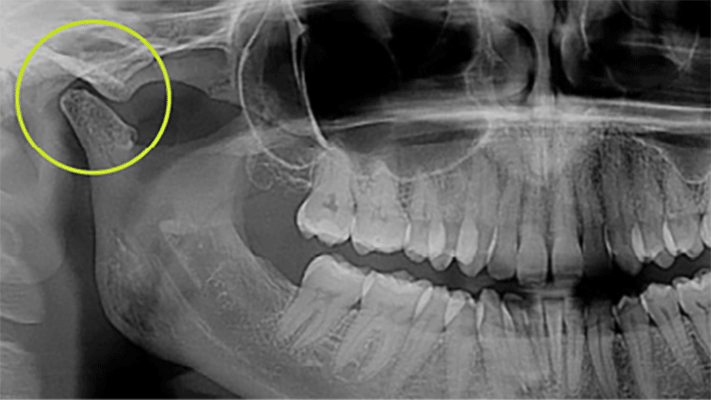

IMG_2625 alternate text for this image

The Urbanek TMJ Device and Protocol announced the official launch of its commercial operations in North America, offering dentists a new way to treat the 10+ million TMD/TMJ sufferers in the United States. “After more than 4,000 cases treated with a 95% success rate, we’re excited to finally offer this solution nationwide to treat the … Read more